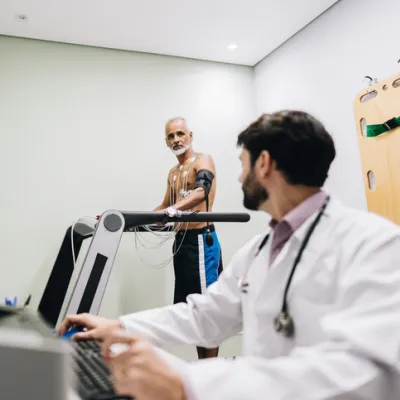

A stress echocardiogram, also known as a stress echo evaluates the effects of exercise on the heart by evaluating how the electrical signals on an electrocardiogram (EKG) change with exercise and also...

A treadmill stress test, also known as a stress electrocardiogram (EKG) evaluates the effect of exercise on the heart by evaluating how the electrical signals on an EKG change with exercise. We also...